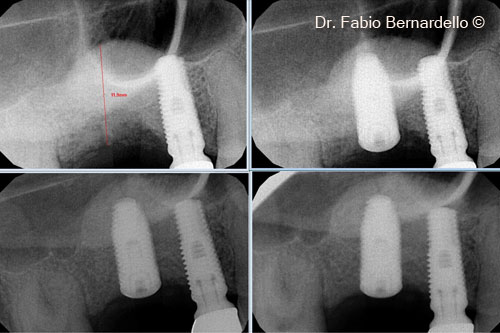

Ảnh chụp X-Quang trước phẫu thuật. Một trụ Implant đã được cấy ghép để thay thế răng số 16 khoảng 10 năm trước

Phim chụp X-quang trong miệng: trong quá trình phẫu thuật tại thời điểm T0 2 tháng và 5 tháng

Hình ảnh X-Quang 7 tháng 6 phẫu thuật cho thấy Gel 40 đã được tái tạo thành xương mới phía trên vùng cấy ghép mới

Hình ảnh X-Quang 7 tháng 6 phẫu thuật cho thấy Gel 40 đã được tái tạo thành xương mới phía trên vùng cấy ghép được đặt 10 năm trước

1 năm sau phẫu thuật, phim X-Quang khó có thể xác định ranh giới giữa xương nguyên thủy và xương mới hình thành.